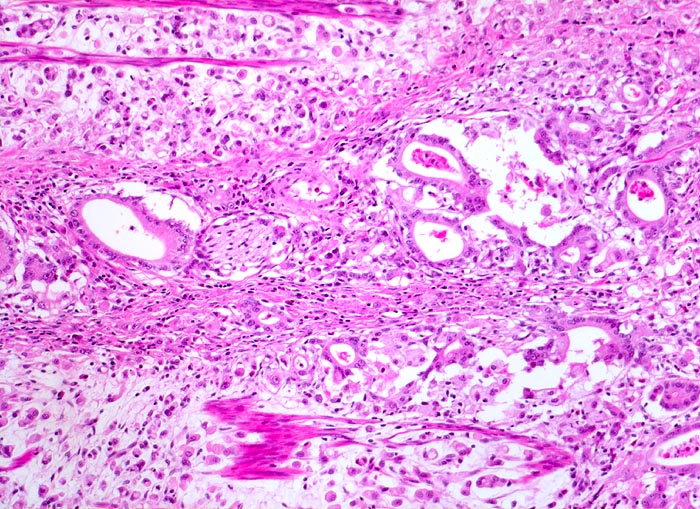

Adenokarzinom des Magens mit Siegelringzellen

Ein Grossteil des Tumorinfiltrats besteht aus einzeln liegenden Siegelringzellen. Ein Teil der Tumorzellen bildet Drüsenschläuche (Mischtyp nach Lauren). Tumorinfiltration einer Nervenscheide. Zwischen den Tumorzellen Reste der glatten Muskulatur der Magenwand.

Der histologische Subtyp eines Siegelringzellkarzinoms darf dann diagnostiziert werden, wenn die Siegelringzellen mindestens 50% der Tumormasse ausmachen.